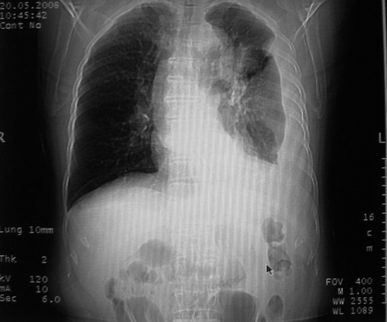

以下是引用zhangzhongshou在2008-5-22 12:51:00的发言:[br]左肺上叶肺癌并左侧胸腔积液可能性大。

以下是引用w_jianhua在2008-5-22 12:59:00的发言:[br]1.左肺上叶肺癌并左侧胸腔积液可能性大。2不除外支气管内膜结核并包裹性胸腔积液,建议支气管镜检3.左肺下叶肺大泡,肺气肿